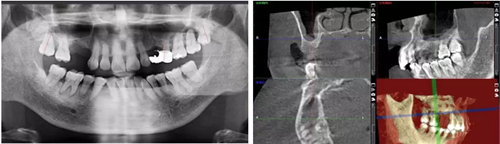

病例賞析 | 上頜竇外提升長期成骨觀察(二)

術(shù)后當(dāng)天 術(shù)后7個月